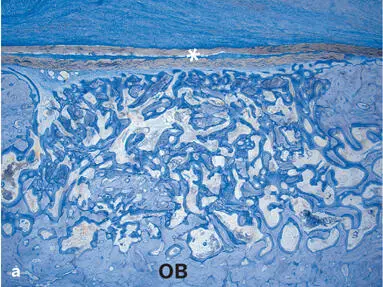

Fig 2-23Histologic sections illustrating standardized bone defects in the minipig mandible (undecalcified ground sections; toluidine blue stain). Old bone (OB) and an ePTFE membrane (asterisks) delineate the defects. The defects were filled with autogenous bone. (a) Particulate from corticocancellous bone with a bone mill. (b) Bone chips harvested with a bone scraper. (c) Bone particles harvested with a piezoelectric instrument. (d) Bone slurry from a bone trap filter. After 4 weeks of healing, all types of autogenous bone grafts are embedded in a trabecular network of new bone that completely fills the defect areas.